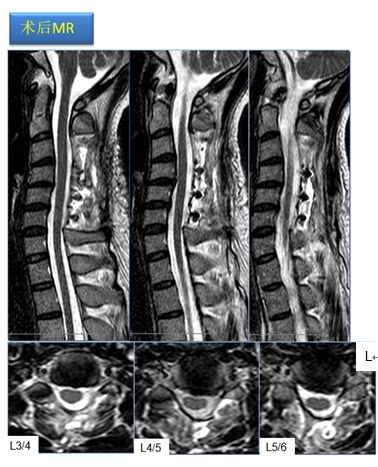

腰椎X线正位L5/S1间隙塌陷,动力位未提示存在椎间失稳;核磁可发现L5/S1椎间盘后方中央突出并压迫神经。

结合患者的症状、体格检查及影像学资料,诊断为腰椎间盘突出症(L5/S1)。

该手术在梁徳主任指导下由江晓兵副教授按照标准化流程顺利完成,将致压髓核进行了彻底摘除,神经压迫顺利解除。术后复查如下:

术后影像学提示可见L5/S1突出物已被完全摘除,神经减压良好。